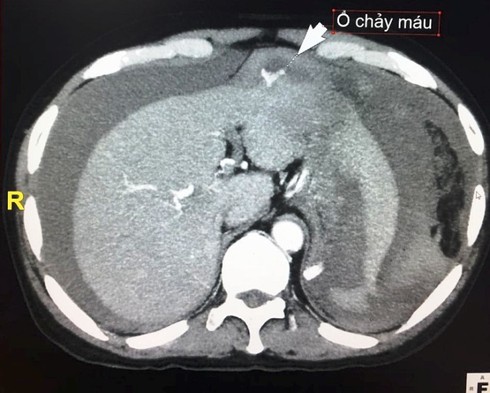

Khối u gan bị vỡ, khiến hơn 2 lít máu tràn ra ổ bụng. |

Qua thăm khám, các bác sĩ phát hiện anh T. bị vỡ u gan hạ phân thùy III và có hơn 2 lít máu trong ổ bụng. Các bác sĩ vừa tiến hành truyền máu và các chế phẩm thay thế máu vừa điều trị bằng phương pháp nút mạch. Sau đó, tiến hành chọc dẫn lưu ổ bụng rút ra 2 lít máu.

Bác sĩ Nguyễn Đức Hùng - Trưởng khoa Chẩn đoán hình ảnh, Bệnh viện Việt Nam - Cu Ba, Đồng Hới cho biết, đây là trường hợp vỡ u gan do chấn thương mà trước đó bệnh nhân không biết mình bị bệnh. Qua kết quả xét nghiệm cho thấy bệnh nhân bị u gan trên nền xơ gan.